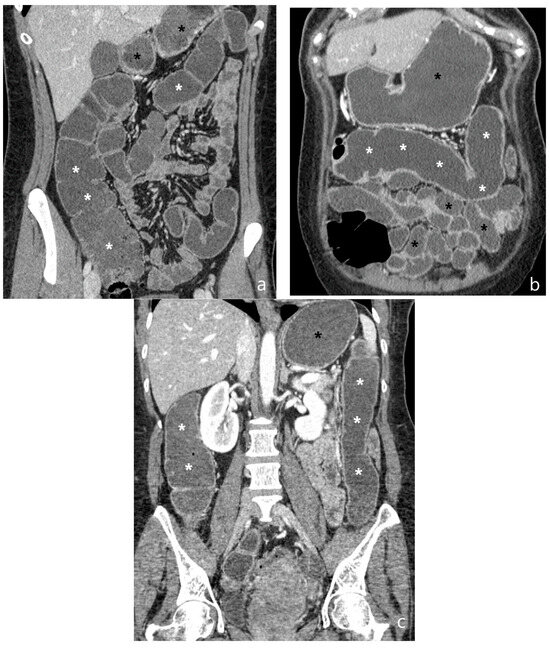

5.2. Fibro-Stenotic Subtype